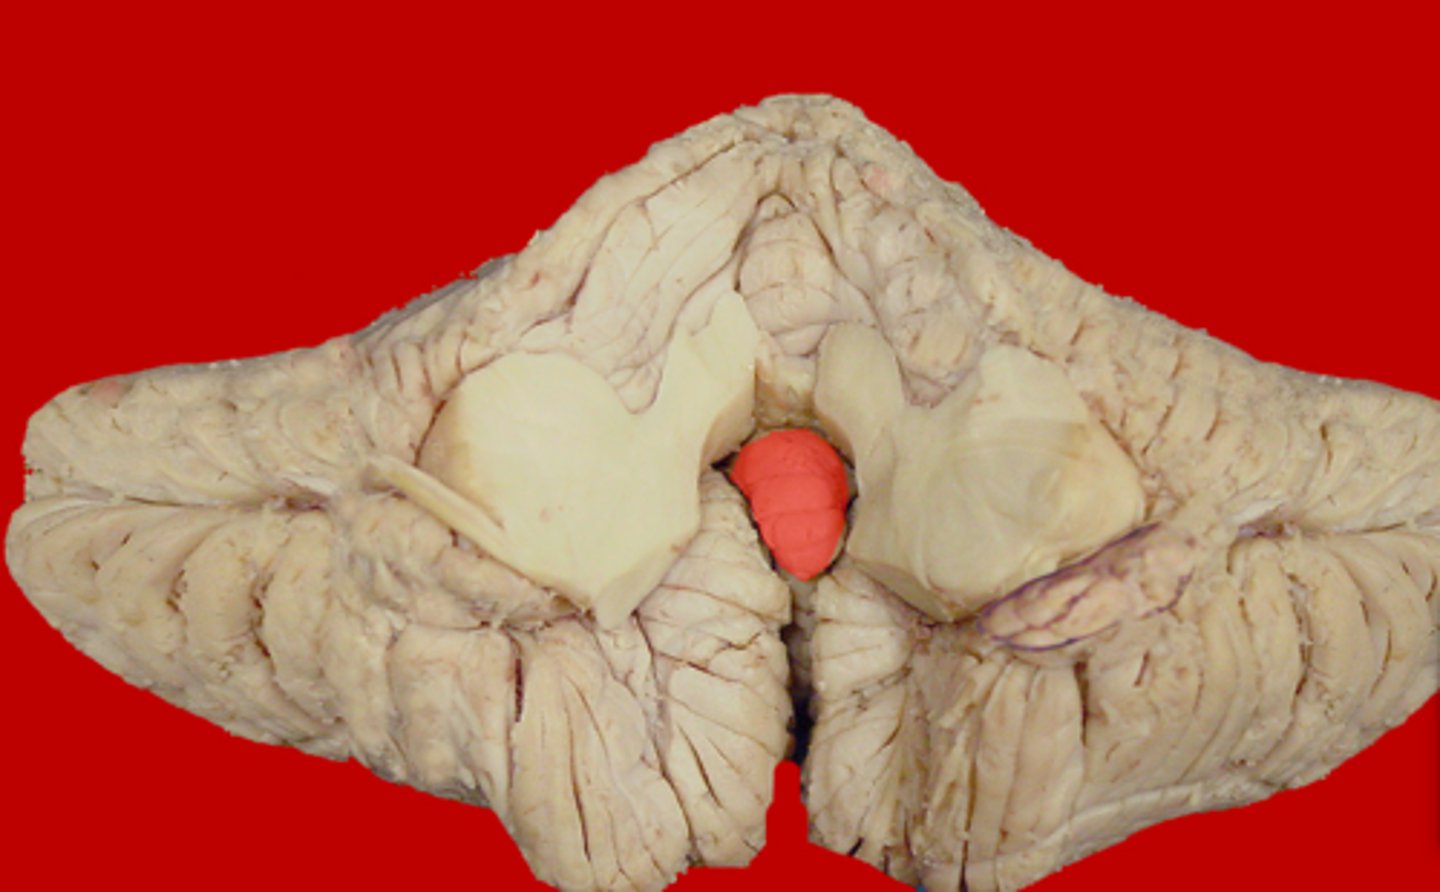

Flocculonodular Lobe

A region of the cerebellum; involved in control of postural reflexes

Flocculus

Nodule

Medial protrusion seen on the midsagittal view of the cerebellum; part of the vermis

Tonsil of Cerebellum

Two elevated masses on inferior surface of hemispheral portion just nearby foramen magnum

Can herniate into the foramen magnum, exerting pressure on the medulla

Composed of flocculonodular lobe

Controls eye movement and axial musculature related to balance and posture

Connects two hemispheres of cerebellum